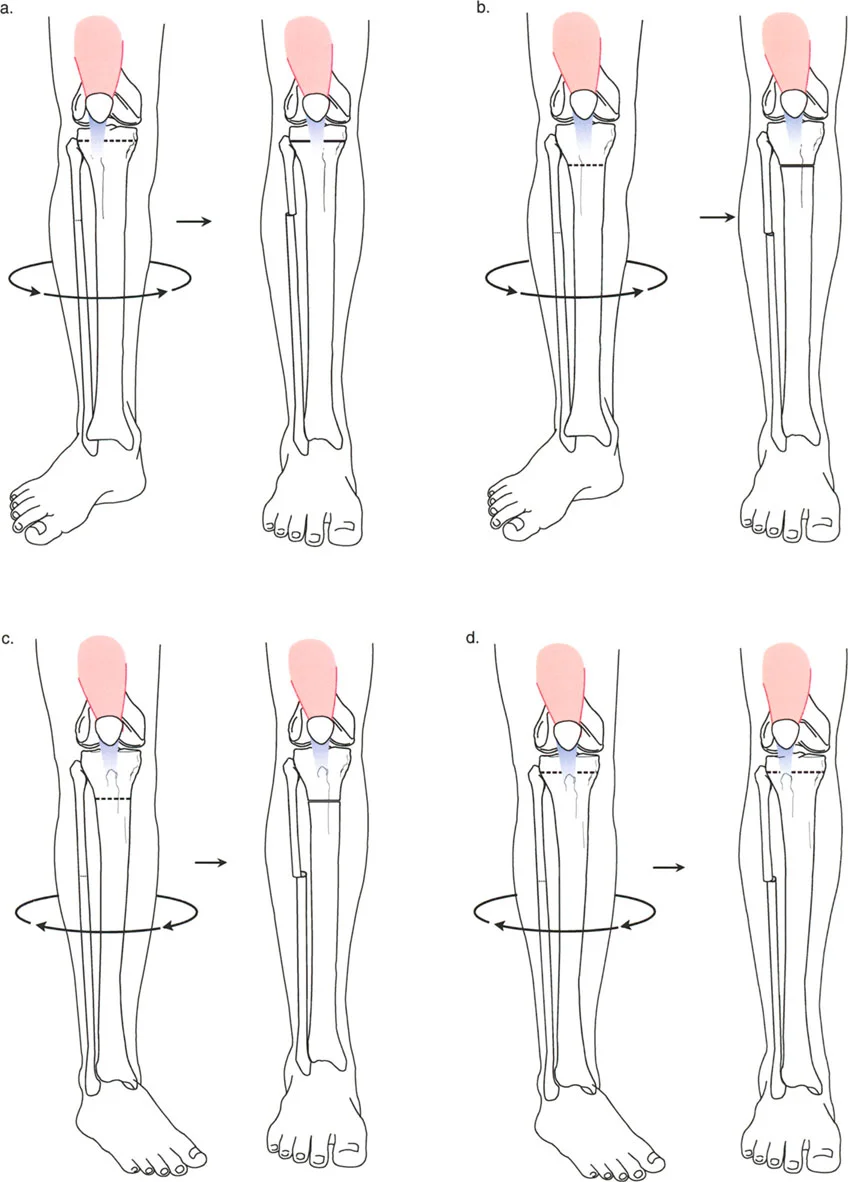

* تشوه الدوران: يعني أن العظم ملتف حول محوره الطولي، مثل لوي قطعة قماش. قد يكون الفخذ ملتفاً للداخل أو للخارج، أو قصبة الساق ملتفة، مما يجعل القدم تتجه للداخل أو للخارج بشكل غير طبيعي عند المشي.

* تشوه الانحراف الزاوي: يعني أن العظم منحني بزاوية غير طبيعية، إما للداخل (تقوس) أو للخارج (تفحج)، أو للأمام أو للخلف.

غالباً ما تتواجد هذه التشوهات معاً، مما يجعل الحالة أكثر تعقيداً. فمثلاً، قد يكون عظم الفخذ منحنيًا وفي نفس الوقت ملتفاً. هذا التداخل يخلق "تشوهاً ثلاثي الأبعاد" يتطلب فهماً عميقاً وكفاءة عالية لتصحيحه.

عندما يكون العظم مشوهاً في كل من الانحراف الزاوي والدوران، فإن أي محاولة لتصحيح أحد الجانبين دون الآخر قد تؤدي إلى نتائج عكسية أو حتى مضاعفات خطيرة. على سبيل المثال:

* إذا قمت بتصحيح الانحناء فقط وتجاهلت الدوران، فقد يظل المريض يعاني من مشكلة في المشي أو ألم في الركبة.

* إذا تم تصحيح الدوران بشكل خاطئ أو في مستوى غير صحيح، فقد يؤثر ذلك على عمل العضلات المحيطة، خاصة عضلات الفخذ الأمامية (الرباعية)، مما قد يؤدي إلى خلع صابونة الركبة أو تآكل غضروف الركبة (تلين الغضاريف).

* يمكن أن يؤدي التصحيح غير الدقيق أيضاً إلى شد غير طبيعي على الأعصاب والأوعية الدموية، مما قد يسبب تلفاً عصبياً مثل شلل العصب الشظوي، وهو ما يؤثر على القدرة على رفع القدم.

* الدوران الظنبوبي (Tibial Torsion): التواء في عظم قصبة الساق، يمكن أن يكون داخلياً أو خارجياً، ويؤثر على اتجاه القدم.

* التئام الكسور الدوراني (Rotational Malunion): إذا التئم كسر في عظم طويل (مثل الفخذ أو قصبة الساق) بينما كانت أجزاء العظم ملتفة بالنسبة لبعضها البعض، فسيؤدي ذلك إلى تشوه دوراني دائم.

* التئام الكسور الزاوي (Angular Malunion): إذا التئم الكسر بزاوية غير صحيحة، فسيحدث انحناء في العظم.